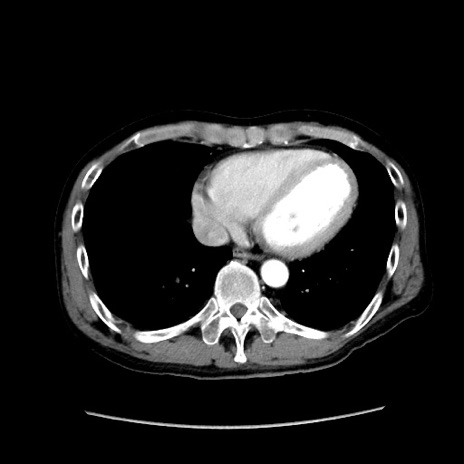

冠状断像

【症例】40歳代 男性

【主訴】腹痛

【現病歴】4時間ほど前に電車に乗車中に臍部上より腹痛出現。徐々に増悪し起立困難となり、救急外来受診。生ものは数日食べていない。今朝お雑煮を食べた。

【身体所見】BT 36.8℃、BP 117/84mmHg、HR 91/min、SpO2 97%、苦悶様、腹部:臍上部広範囲圧痛あり、反跳痛±

【データ】WBC 8100、CRP 0.03